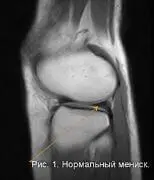

Мениски разделяются на медиальный (внутренний) и латеральный (наружный). Нормальный мениск на МРТ–изображениях выглядит однородным, с пониженным сигналом, то есть темным. Вид нормального мениска представлен на рисунке №1. Стрелкой указан задний рог, в виде треугольного, темного участка, однородной структуры. Спереди визуализируется передний рог.